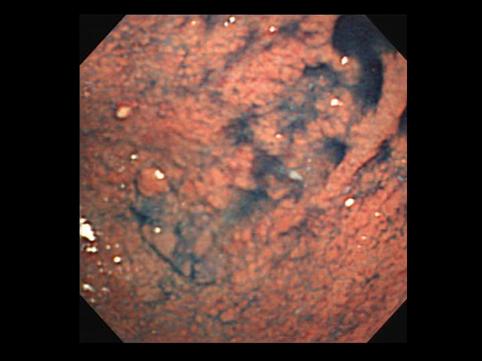

疾病(病理主体)的分类恶性上皮性肿瘤/腺癌

部位(按器官分)胃(部位)/2个以上

检查方法内窥镜

肿瘤的肉眼分类0型(表在型)/IIb型(IIb+IIa)

肿瘤最大直径40以上

肿瘤的深度m